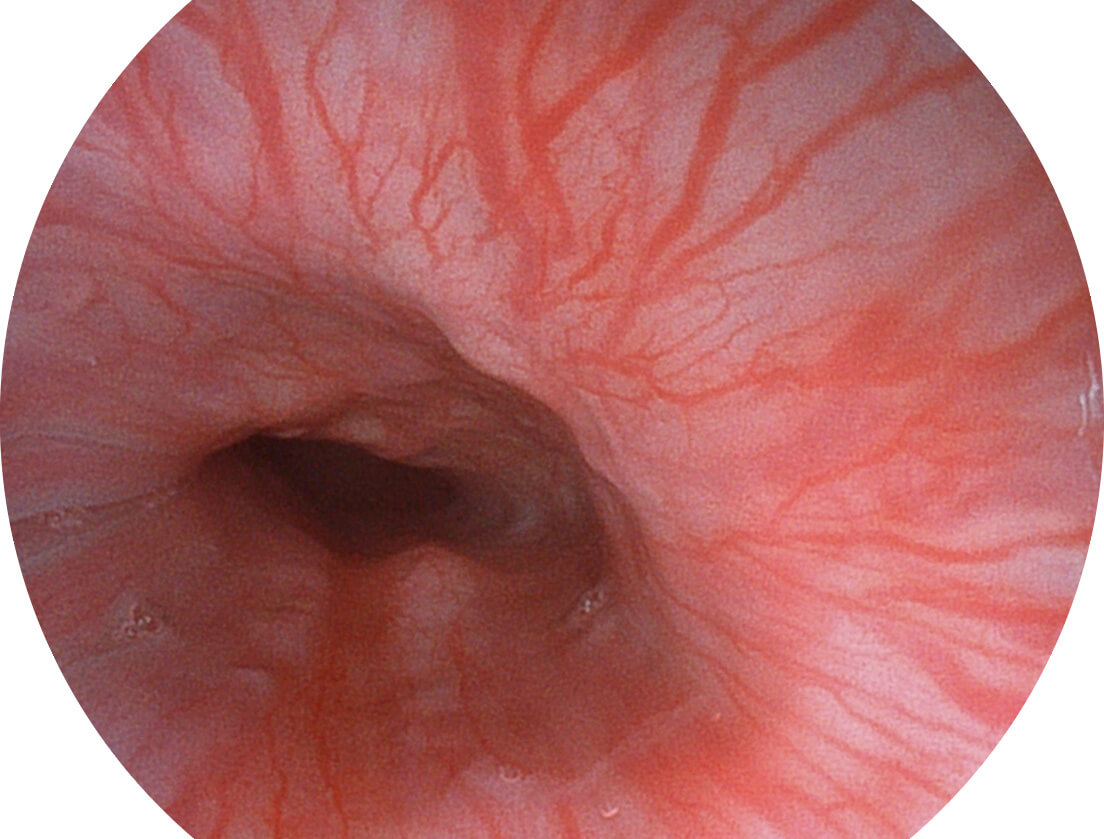

• 白光图像 SFI图像